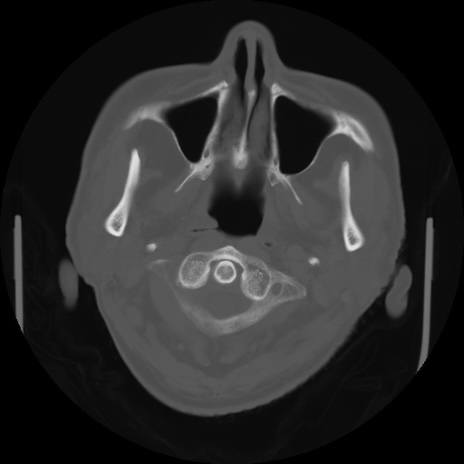

【頭部】症例5 CT(横断像)

【症例】80歳代 男性

【主訴】頭部打撲

【現病歴】外出先で椅子から立ち上がる際に、つまづいて後方へ転倒し受傷。転倒時に意識はあった。

【既往歴】高血圧、不整脈、アルツハイマー病

【身体所見】BP 217/71、HR 96、JCS1-1、 難聴あり、顔色良好、右後頭部に擦過創あり。神経学的異常なし。

症例5の画像所見と診断は?